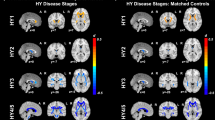

Figure 1 shows an example of an STN segmentation. The mean raw STN volume was 122 ± 18mm3 for the healthy control subjects (right volume = 124 ± 19mm3; left volume = 121 ± 17mm3) and 110 ± 17mm3 for the PD group (right volume = 110 ± 18mm3; left volume = 111 ± 16mm3) (Fig. 2).

STN volume differences between the two groups. Blue indicates data for the PD group. Orange indicates data for the healthy control group. EPD = early Parkinson’s disease group. STN = subthalamic nucleus. * = Statistical significance p < 0.05 from a linear mixed model effect. The 25th and 75th percentiles are represented by the lower and upper boundaries of each box with median values represented by the middle band within the box.

In the first linear effects model, both healthy control and PD groups were included to model normalized STN volume. The normalized STN volumes were 116 ± 13 mm3 for the controls and 103 ± 17 mm3 for the PD group. Age, sex, side and STN FA were considered as adjusting variables, but their effects were not statistically significant (p > 0.10) and were removed from the model. The effects of group were statistically significant and were retained in the model. The model estimated difference in normalized STN volume between healthy control and PD groups was found to be 12mm3 (95% confidence interval3,21, t = −2.67, df = 45, p = 0.01, regression coefficient = −12.3), indicating an 11.2% smaller average normalized STN volume in the PD group compared to the healthy controls.

In the second linear effects model, factors contributing to the normalized STN volume in the PD group were examined. Age, sex, side, and STN FA were considered as adjusting variables, but their effects were not statistically significant (p > 0.077). There was an inverse relationship between clinical measures of motor severity (total MDS-UPDRS III score) and normalized STN volume (i.e. participants with increased motor severity had decreased STN Volume) but this relationship across PD participants did not reach statistical significance (p = 0.056). Lateralized MDS-UPDRS III scores were used in a separate model but the results were not statistically significant (p = 0.13).

STN FA

Mean STN FA values were 0.36 ± 0.09 for the PD group and 0.43 ± 0.11 for the healthy control group (Fig. 3). No significant difference in STN FA was observed between the left and right sides for both groups (p = 0.50). Age, sex, side and normalized STN volume were considered as adjusting variables, but their effects were not statistically significant (p > 0.08). Only the effect of subject group was statistically significant. The model estimated difference in STN FA between the healthy control and PD groups was found to be 0.07 (95% confidence interval [0.02, 0.12], t = −2.76, df = 45, p < 0.008, regression coefficient = −0.07), indicating a 19% higher average FA in the control subjects compared with the PD group.

STN-FA differences between the two groups. Blue indicates data for the PD group. Orange indicates data for the healthy control group. FA = fractional anisotropy. EPD = early Parkinson’s disease group. STN = subthalamic nucleus. * = Statistical significance p < 0.05 from a linear mixed model effect. The 25th and 75th percentiles are represented by the lower and upper boundaries of each box with median values represented by the middle band within the box.

In the second statistical model, factors contributing STN FA in the PD group were examined. Adjusting factors of age, sex and side were not significant. The factor of MDS-UPDRS III score was also not significant (p = 0.10). The adjusting factor of STN volume was statistically significant (t = −2.67, df = 28 p = 0.01, regression coefficient = −0.002). An inverse association between normalized STN volume and STN FA was observed. Lateralized MDS-UPDRS III scores were used in a separate model but the results were not statistically significant (p = 0.41).